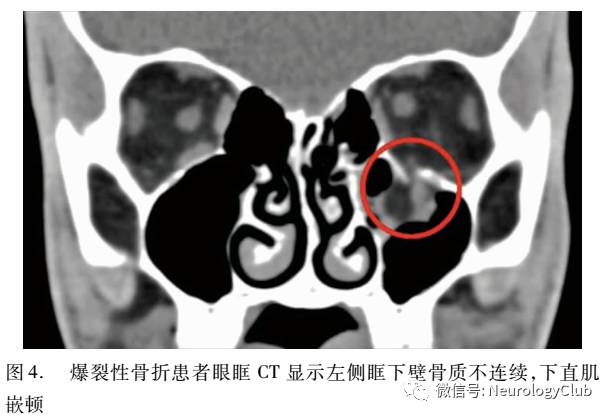

爆裂性骨折警惕爆裂伤后单眼运动受限/眼球固定,需要做进一步的影像学(CT)检查(图4)。